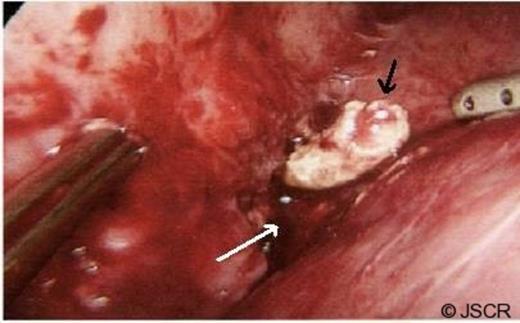

She underwent diagnostic laparoscopy which revealed an abscess cavity in the image identified location. Once the peritoneum was opened purulent fluid discharged and on exploration of the cavity the faecolith was found (Figure 2). The faecolith was removed and abscess drained. A 20 Robinson drain was placed in the cavity until the following morning. The patient’s post-operative course was uneventful and she was discharged home the following day in a stable condition, afebrile and with normal serum inflammatory markers.

Appendicolith (black arrow) in the perihepatic abscess cavity (white arrow).